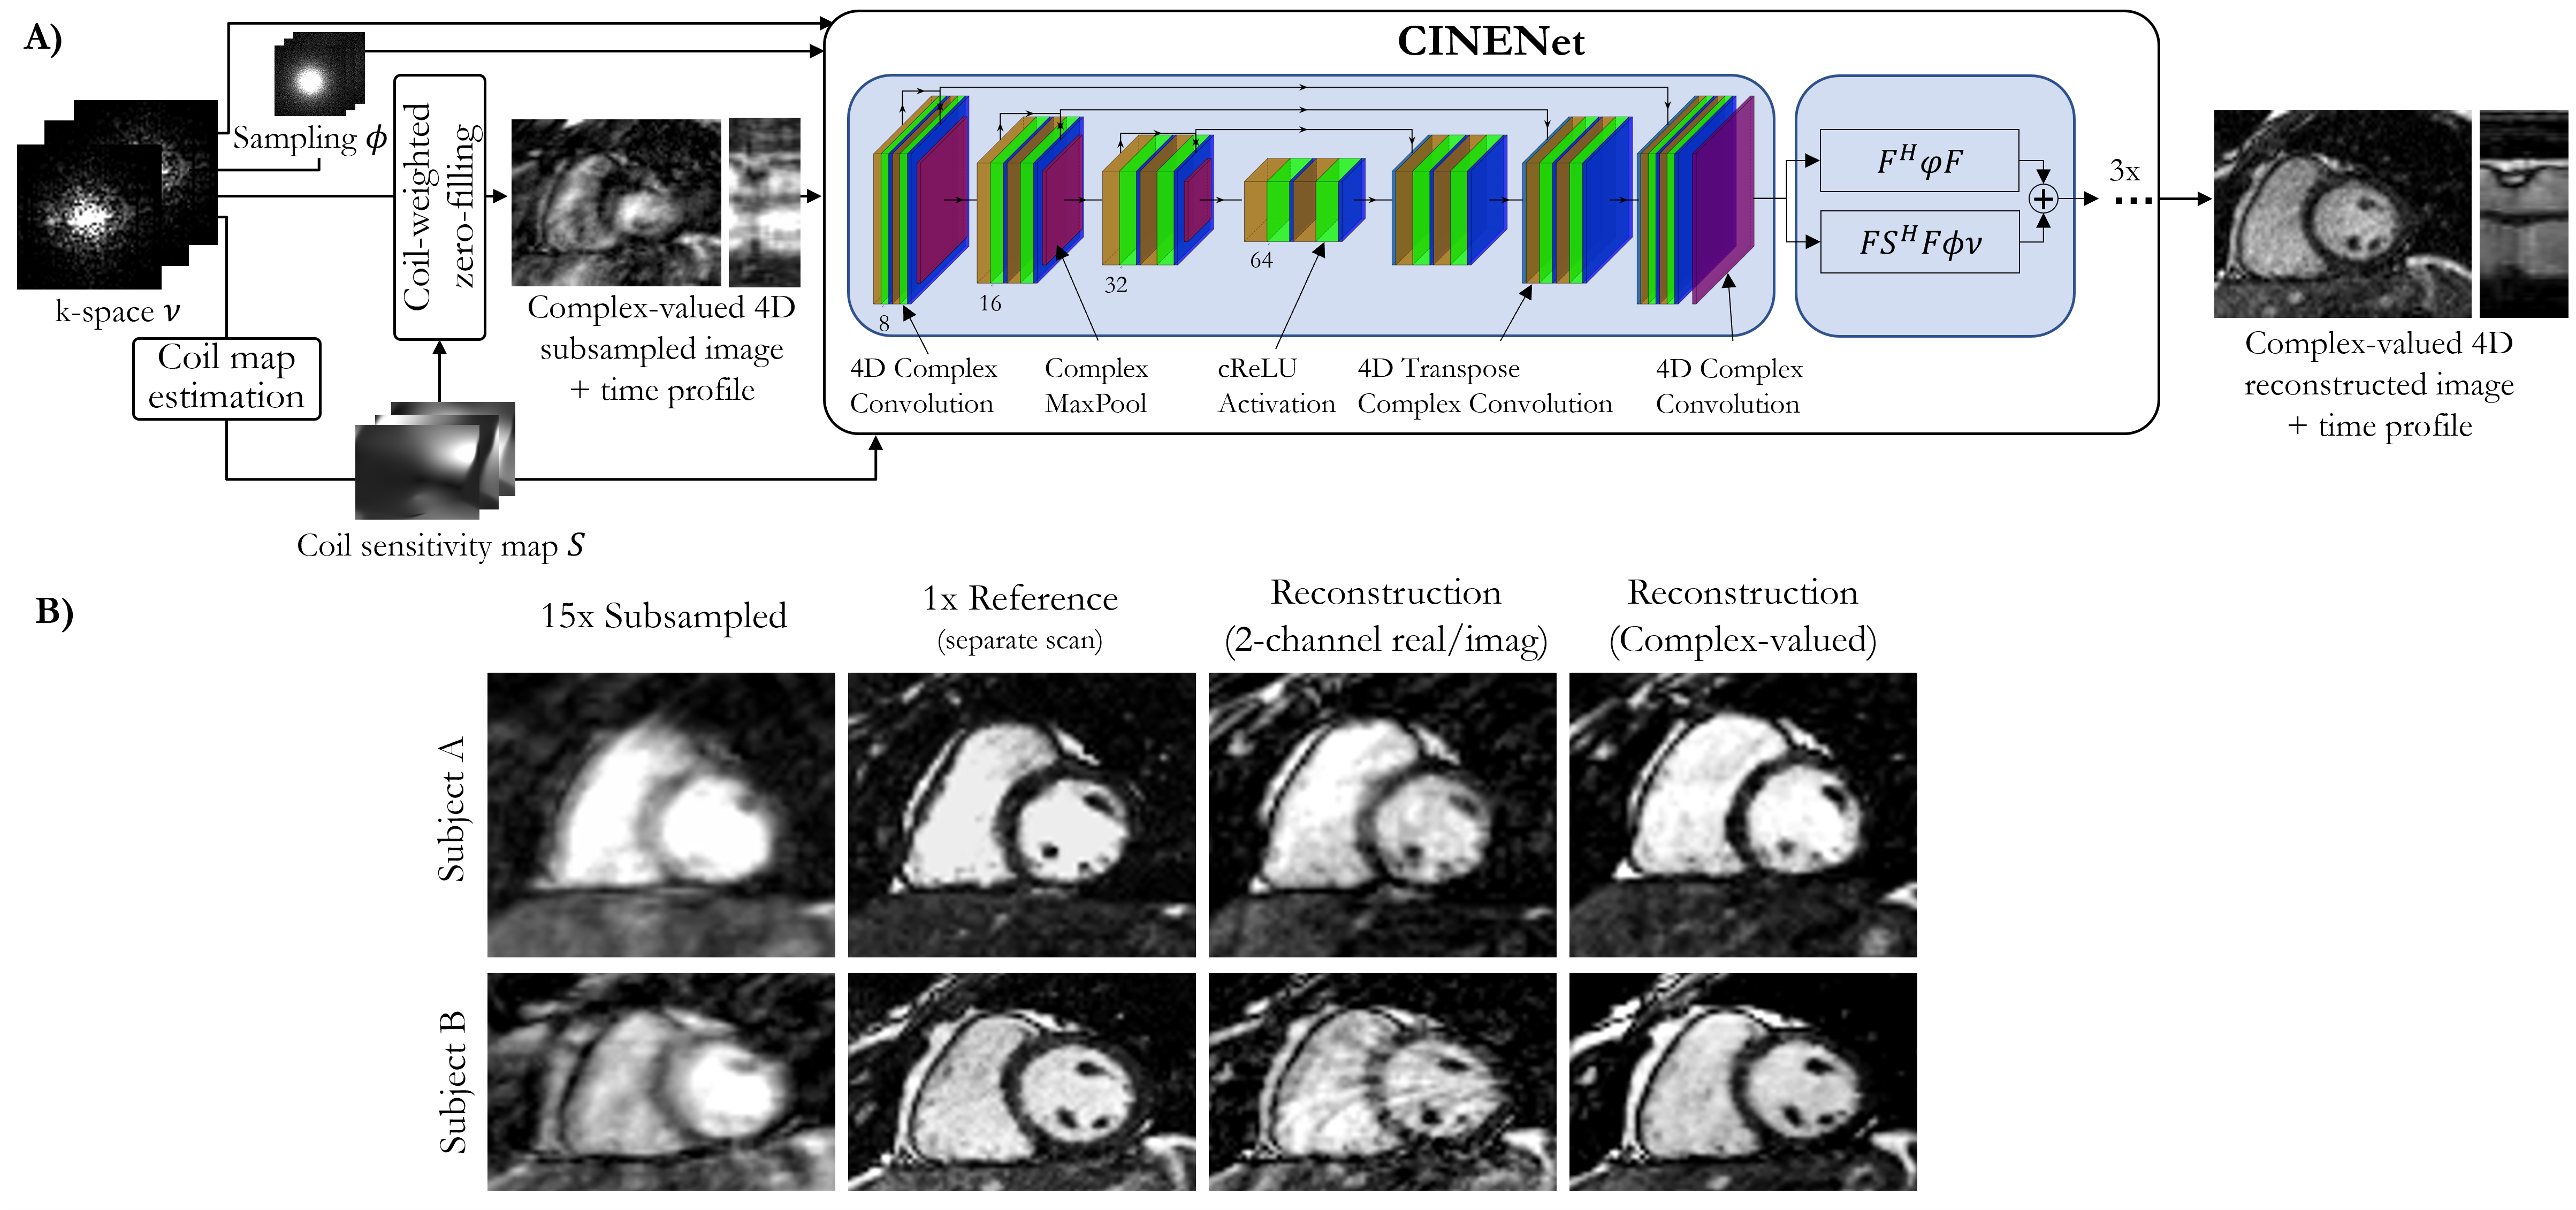

All previously mentioned approaches consider the complex-valued MR images as images with two real-valued feature channels. CINENet [80] combined both data consistency layers with complex-valued building blocks as depicted in Figure 5, for dynamic 3D (3D+) data. These complex-valued building blocks include convolutions, activations, pooling, and normalization layers. To process the 3D+ in the regularization network, convolution operations are split into 3D spatial convolutions, followed by 1D temporal convolutions.